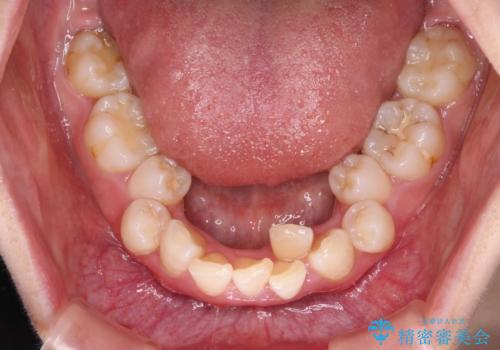

叢生・ディープバイト・突出 ワイヤー装置での抜歯矯正で全てを解決

- 前歯のデコボコと唇の閉じにくさを気にして来院された患者様です。

極端な出っ歯という訳ではありませんでしたが、叢生が強かったため、上下左右の第一小臼歯4本を抜歯し、少しでも口元の突出感を改善できるよう治療計画を立案しました。

下顎前歯が隠れるほどのディープバイトであり、それによる顎の負担も大きかったため、ディープバイトもしっかりと改善できるよう、表側のワイヤー装置にて矯正治療を行うこととしました。